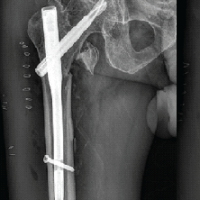

Figure 1: Intraoperative picture and Halifax nail instrumentation.

All patients were discharged on day 5 after the 2nd post-operative dressing. All patients were reviewed every 15 days for the first 2 months and monthly from the 2nd month to the 6th month. The union status was checked by every monthly radiograph of anteroposterior and lateral views of the affected hip and thigh. Modified Harris hip score was used for all patients at the 3rd and 6th months of follow-up to evaluate the functional outcome (Fig. 2).

Figure 2: X-rays and post-operative functional movements.